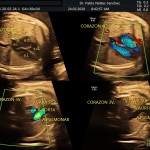

- Las estructuras anatómicas fetales: diagnóstico de Malformaciones Estructurales de aparición tardía (displasias esqueléticas, alteraciones cardiacas pequeñas, alteraciones la vía urinaria y obstrucciones intestinales.